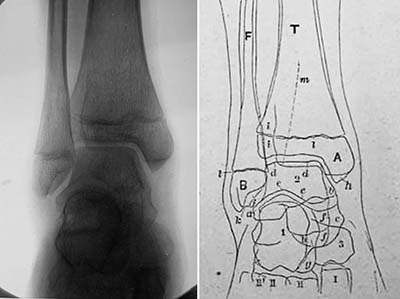

《1918-20-正常四肢骨のレントゲン写真図譜》

藤浪剛一(朝香屋書店,1918-20)

藤浪は序文で,欧米のようなレントゲン図譜が本邦にはないことを憂い,かねてよりこれを企画していたものの,出版者が写真を鮮明に印刷する技術を持たず実現できなかったが,本書の出版社である朝香屋の主人がこれを引き受けてくれてようやく発刊できたと述べている.レントゲン図譜と銘打っているが,その内容は専ら四肢骨の正常像で,小児の骨化中心の出現に主眼が置かれている.藤浪は,ウィーン留学中に手根骨の骨化順序に関する論文を2篇著しており,その延長上にあるものと思われる.

第一輯から第四輯まで四分冊で,それぞれ手関節,肘・肩関節,足関節,膝関節の正常像を扱い,全58葉のレントゲン写真とそのスケッチが,小児から成人まで年齢順に供覧されている(図10,図11).写真の画質はかなり良好で,現在でも充分通用する解像度を備えている.

藤浪の著書で,放射線診断学領域を扱ったものは,本書の他には「内臓レントゲン診断学」および「れんとげん学」があるが,胸腹部の内臓疾患については詳細に書かれているものの,奇妙なことにそのいずれも骨格系の診断については全く触れていない.欧米では既にこの時期,骨折や骨端症の画像所見が数多く報告され,教科書も書かれていることを考えると疑問に思うところであるが,藤浪は特にこの点について言及していない.その意味で本書は,正常像のみであるが骨格系のレントゲン像を記載した唯一の著書である.